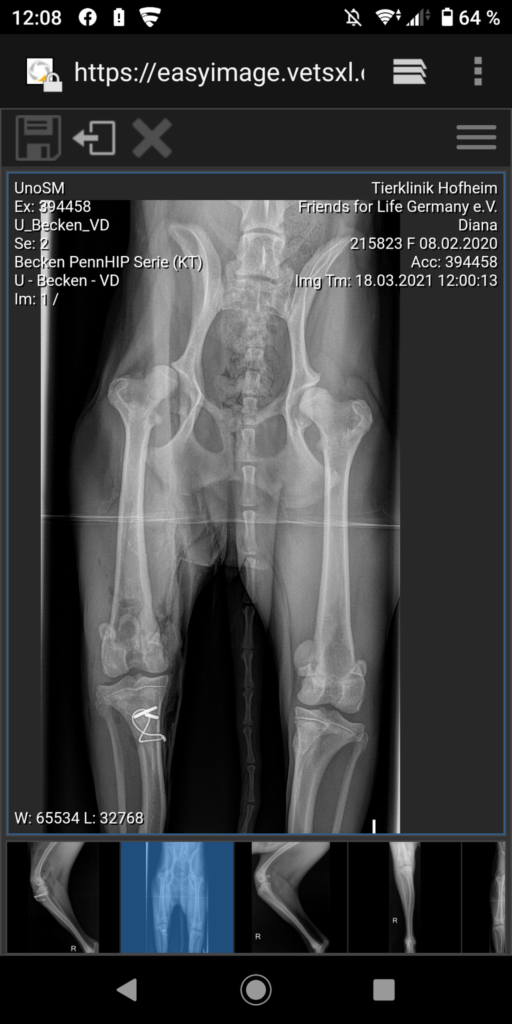

Diana wurde als Junghund im Karton an einer Straße in Rumänien gefunden. Auffällig war von Anfang an, dass sie ein Problem mit den Knien hatte. Zunächst wurde sie von der Tierschützerin in Rumänien aufgepäppelt und erhielt die nötigen Impfungen. Seit Ende Februar 2021 ist sie nun in Deutschland auf einer Pflegestelle und wurde mittlerweile hier an beiden Knien operiert. Sie hatte eine angeborene Kniescheiben – Luxation. Endlich hat sie alles gut überstanden. Diana ist allerdings immer noch sehr ängstlich Fremden gegenüber, warum bisher keine Adoption möglich war. Sie hat in ihrem Leben nicht viel Gutes erfahren und kennen lernen dürfen und reagiert daher auch in einigen Alltagssituationen ängstlich. Zu ihrer Bezugsperson in Deutschland hat sie vollstes Vertrauen aufgebaut. Sie ist gut verträglich mit den anderen Hunden auf der Pflegestelle. Auch Katzen sind kein Problem. Gesucht werden Menschen, die die nötige Geduld haben, Diana den Weg in ein „normales“ Hundeleben zu zeigen, und auch die entsprechenden Möglichkeiten haben zunächst nichts von ihr zu erwarten. Ein sicher eingezäunter Garten und die Möglichkeit des selbständigen Zugangs wäre Bedingung. Grundsätzlich ist Diana ein aktiver Hund.